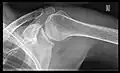

X-ray

Projectional radiography views of the shoulder include:

- AP-projection 40° posterior oblique after Grashey

The body has to be rotated about 30 to 45 degrees towards the shoulder to be imaged, and the standing or sitting patient lets the arm hang. This method reveals the joint gap and the vertical alignment towards the socket.[24]

- Transaxillary projection

The arm should be abducted 80 to 100 degrees. This method reveals:[24]

- The horizontal alignment of the humerus head in respect to the socket and the lateral clavicle in respect to the acromion

- Lesions of the anterior and posterior socket border, or of the tuberculum minus

- The eventual non-closure of the acromial apophysis

- The coraco-humeral interval

- Y-projection

The lateral contour of the shoulder should be positioned in front of the film in a way that the longitudinal axis of the scapula continues parallel to the path of the rays. This method reveals:[24]

- The horizontal centralization of the humerus head and socket

- The osseous margins of the coraco-acromial arch and hence the supraspinatus outlet canal

- The shape of the acromion

This projection has a low tolerance for errors and, accordingly, needs proper execution.[24] The Y-projection can be traced back to Wijnblath’s 1933 published cavitas-en-face projection.[25]

CR. shoulay film.

Transaxillary conventional radiography

Y-projection conventional radiography